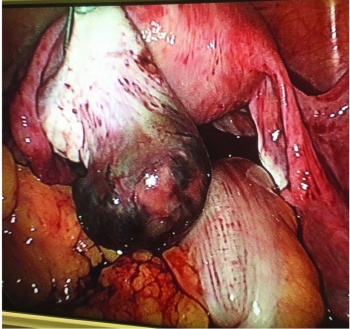

A day after the third level of beta hCG, the patient began complaining of severe lower abdominal pains and became hypotensive with blood pressure 80/45. A laparoscopy was performed due to severe pain and hypotension. Ectopic pregnancy was identified over the left ovary. Uterus, bilateral fallopian and right ovary were normal. There was pelvic haemoperitoneum and no signs of adhesions or Fitz-Hugh-Curtis syndrome (FHCS). Laparoscopic removal of left ovarian ectopic pregnancy was performed by diathermy scissors.